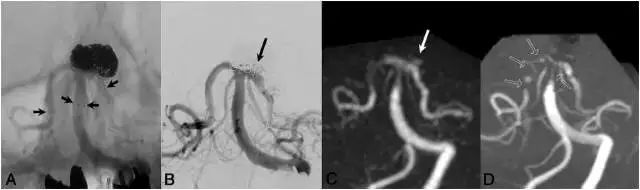

图3,病例3,66岁女性。A:Y型支架辅助的弹簧圈栓塞治疗,右侧PCA使用Neuroform支架,左侧PCA使用Enterprise支架,短箭头显示支架边缘;B. 当天进行DSA检查,可见颈部残留(长箭头所示);C. Silent MRA图像,可见轻度信号丢失,可见颈部残留(长箭头所示);D. 同一天进行TOF-MRA检查,在基底动脉观察到中等强度的信号丢失,双侧PCA段可见完全的信号丢失(黑箭头)。